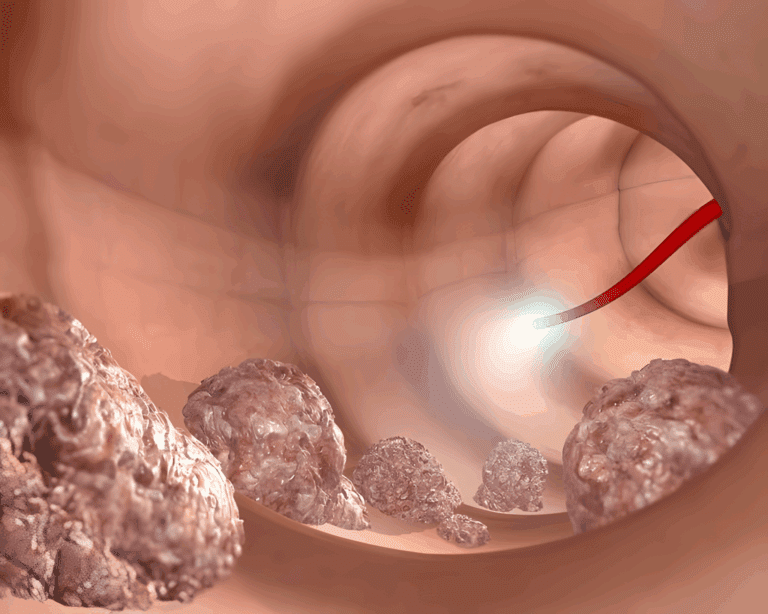

⚠️ Rak jelita grubego: objawy, których nie należy ignorować Rak jelita grubego (znany również jako rak jelita grubego) jest jedną z najbardziej śmiertelnych form…